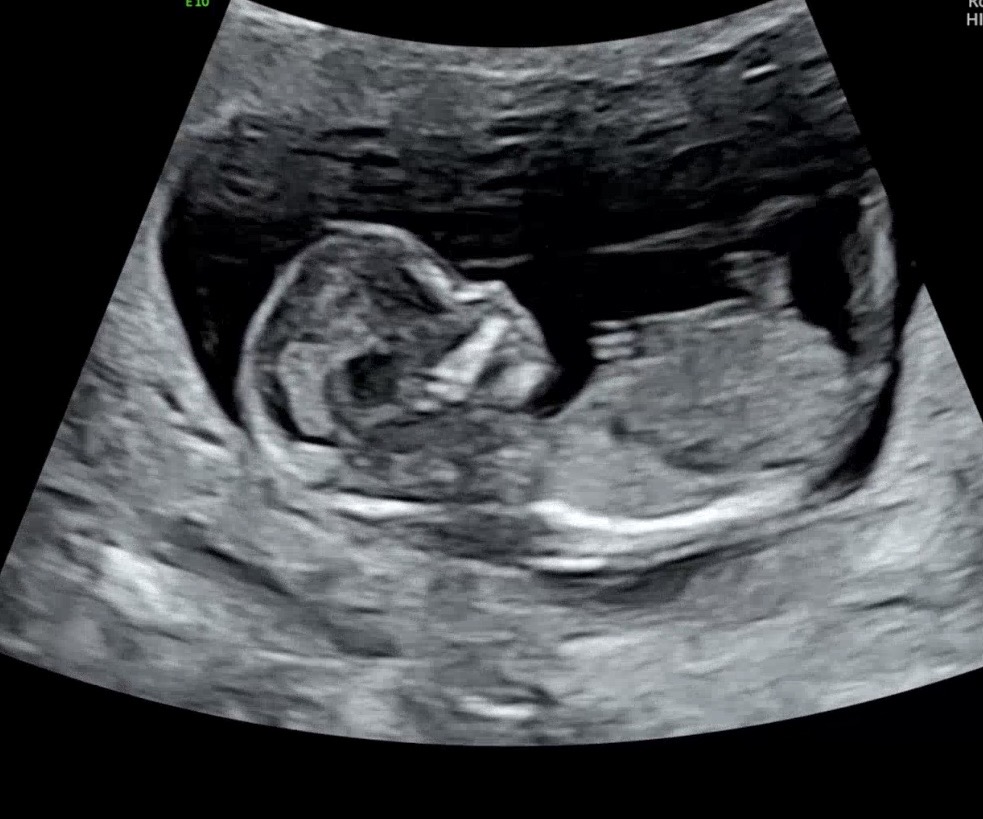

12주 5일 각도법 투표부탁드려요🫶

정밀초음파받고왔는데 성별 너무궁금해지네요😀 태몽은 아들꿈이구 주변에서 다 아들예측하는데 각도법으로 보면 딸일지,아들일지 너무 궁금하네요 투표너무감사해요 🫶빌리에서는 딸예측나왔었는데 오늘 니프티 결과나왔는데 아들이라고하네요 ❤️